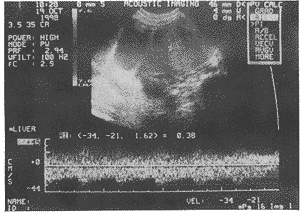

图1 子宫浆膜下肌瘤

阔、骶韧带平滑肌瘤组瘤体内血流非常丰富呈网状和条状,子 宫浆膜下肌瘤组血流丰富呈条状和点状,子宫肌壁间肌瘤和阴道壁肌瘤血流较丰和不丰呈星 状或点状(图1~3)。瘤体内动脉血流参数值见表2。

2.良性盆腔平滑肌瘤亦可出现丰富的低阻力型动脉频谱。本组资料中,部分阔韧带肌瘤以 及少数子宫浆膜下肌瘤和个别子宫肌壁间肌瘤均可检出低阻力型动脉血流,RI≤0.40,且这些平滑肌 瘤瘤体均较大,径线7~22cm(见图1~3)。近年来,恶性卵巢肿瘤内部血流阻力低于良性卵 巢肿瘤的报道甚多,以PI<1.0,RI<0.40作为诊断恶性卵巢肿瘤的分界值已为较多学者 所采纳〔1、3〕,由于阔韧带平滑肌瘤部位特殊,应注意与恶性卵巢肿瘤相鉴别,前 者包块内部回声致密呈旋涡状或形成栅栏征,部分瘤体内可见不规则液性暗区〔2〕 ;后者回声不均,可见光斑光团或暗区,且多伴有腹水,可资鉴别〔1〕。而对于子 宫肌壁间和浆膜下肌瘤,只要重视黑白超声的图像特征,并认识到有出现低阻力型动脉频谱 的可能性,鉴别诊断应当不成问题。